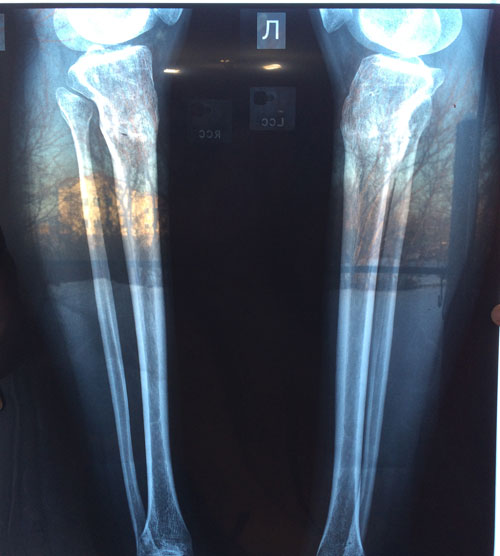

Дата операции 08.10.2015г.

Дата снятие аппаратов 11.12.2015г.

Срок лечения 62 дня.

1,5 МЕСЯЦА с момента снятия аппаратов.

Здравствуйте, А.! Сращение железное, ножки в норме. Вы можете ходить на любой вид спорта, фитнеса, каблуки и т.д. Исключить: беременность в первые 6 месяцев с момента снятия аппаратов.